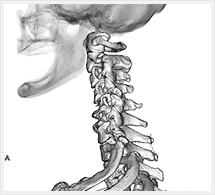

画像紹介

CTでは輪切り像の他にも立体的な画像(3D画像)を作成することもできます。そのためにはより細かくキレイな画像を撮影しなければなりません。当院では64列CTを導入しており、キレイな画像をより細かく撮影することができます。その画像を元に3D画像を作成することによって、より正確な手術のシミュレーションが可能になります。実際に手術をしたときの様子が、手術をする前に画像として見らます。外科系の手術には欠かせない技術となっておりますが、内科系でも血管内手術にも多く利用されております。

当診療放射線技術科では毎日各診療科に対して、その手術に最適な3D画像を提供しております。

以下にその3D画像を一部分紹介します。

頚部